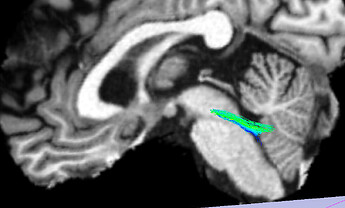

The below screenshot shows a subset (1%) of the 3.5 M streamlines:

Although it is a small fraction it shows the trend IMO.

The extracted MCP looks like this (the sagittal cut is at the midline):

So not quite right either, as streamlines climbs through the SCP and do not travel across the pons. My extraction should not be a problem since it is working OK on other tractography data.